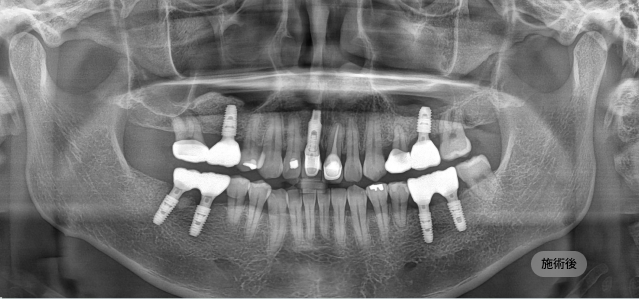

画面をドラッグして前/後を比較してみてください